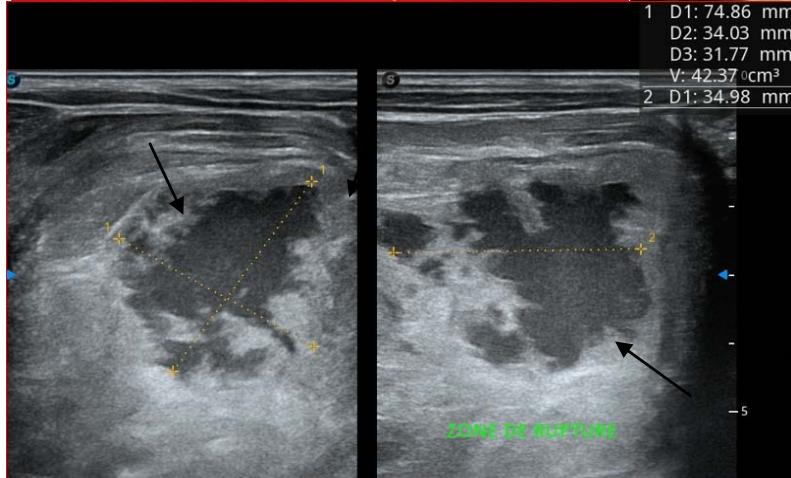

Figure 5: Abdominopelvic ultrasound control after 6 courses of chemotherapy in the same 3 year old patient with a ruptured left renal nephroblastoma; Images A, F, G, and H: show regression of the solid, endo and exo renal, left nephroblastoma mass treated with 6 courses of chemotherapy (current volume 430 ml vs) Images: B, C, and: show persistence of thrombotic permeation pan vena cava and ipsilateral renal. Image E: shows a volumetric regression of the intra-lesional hematic collection, at the tumor rupture estimated at 34.49 ml VS, Image I: represents the right kidney in B mode which is of normal echoculture. Source: Dr. Frederick Tshibasu Tshienda database.